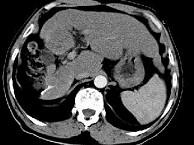

问题 女性,56岁,腹胀、双下肢浮肿、乏力、食欲不振,影像所见如下图,最佳的诊断是()

选项 A.酒精性肝硬化并肝血管瘤 B.血吸虫肝硬化并肝癌 C.肝炎后肝硬化并肝癌 D.局限性脂肪肝 E.原发性肝癌

答案 B